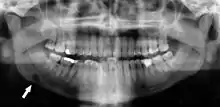

- تشخيص ضرس العقل المنطمر والتخطيط للعلاج. الاستخدام الأكثر شيوعًا هو تحديد حالة أسنان الحكمة وإصابات الفكين.

تتمتع الصور الشعاعية البانورامية بالقدرة على إظهار جزء من الرقبة وعرض التصلب الشرياني (التكلسات في الشريان السباتي) والتي تعتبر مؤشراً على كل من تصلب الشرايين الموضعي والعام. يعد تصلب الشرايين التاجية الذي يؤدي إلى احتشاء عضلة القلب (النوبة القلبية) وتصلب الشرايين السباتية التي تؤدي إلى السكتة الدماغية هي السبب الأول و الأكثر شيوعًا للوفاة في الولايات المتحدة.[5]

عدوى الأسنان وتصلب الشرايين

يعزى تصلب الشرايين إلى عوامل خطر تشمل تدخين السجائر، وفرط شحميات الدم، والسمنة، وداء السكري، وارتفاع ضغط الدم. مع ذلك هذه العوامل لا تمثل بالكامل خطر الإصابة بالمرض. تم تصوُّر تصلب الشرايين على أنه نتيجة التهاب مزمن لإصابة الخلايا البطانيةy[23] والاختلال الوظيفي الذي ربما ينجم عن عدوى الأسنان المزمن. في عام 2010 وباستخدام مؤشر التصوير الشعاعي البانورامي Mattila الذي تم التحقق منه سابقاً لقياس إجمالي العدوى السنية (على سبيل المثال، الآفات المحيطة بقمة الجذر وبين الجذور، التهاب ما حول التاج، جذور الأسنان المصابة بالتسوس، الأسنان مع تسوس وصل للب السن، العيوب العظمية الرأسية)، حددت مجموعة فريدلاندر أن الأفراد الذين يكون لديهم تصلب الشريان السباتي على صورهم البانورامية كان عندهم كميات أكبر من عدوى / التهاب أسنان من عوامل خطر تصلب الشرايين بكثير.[24]قالب:Primary source inline[25]قالب:Primary source inline في حين كان مؤشر Mattila قد استخدم سابقاً لربط مدى انتشار العدوى السنية بـمرض الشريان التاجي، فإن هذا البحث هو الأول الذي يربط بين مجموعة كاملة من أمراض الأسنان التي تقيس الصور الشعاعية البانورامية التي تثبت تصلب الشريان السباتي المتكلس.